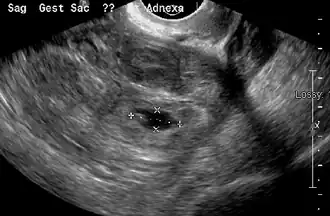

Transvaginal ultrasonography

An ultrasound showing a gestational sac with the fetal heart in the fallopian tube has a very high specificity for ectopic pregnancy. It involves a long, thin transducer, covered with the conducting gel and a plastic/latex sheath and inserted into the vagina.[38] Transvaginal ultrasonography has a sensitivity of at least 90% for ectopic pregnancy.[5] The diagnostic ultrasonographic finding in ectopic pregnancy is an adnexal mass that moves separately from the ovary. In around 60% of cases, it is an inhomogeneous or a noncystic adnexal mass, sometimes known as the "blob sign". It is generally spherical, but a more tubular appearance may be seen in the case of hematosalpinx. This sign has been estimated to have a sensitivity of 84% and a specificity of 99% in diagnosing ectopic pregnancy.[5] In the study estimating these values, the blob sign had a positive predictive value of 96% and a negative predictive value of 95%.[5] The visualization of an empty extrauterine gestational sac is sometimes known as the "bagel sign", and is present in around 20% of cases.[5] In another 20% of cases, there is visualization of a gestational sac containing a yolk sac or an embryo.[5] Ectopic pregnancies where there is visualization of cardiac activity are sometimes termed "viable ectopic".[5]

A pregnancy not in the uterus[39]

The combination of a positive pregnancy test and the presence of what appears to be a normal intrauterine pregnancy does not exclude ectopic pregnancy, since there may be either a heterotopic pregnancy or a "pseudosac", which is a collection of within the endometrial cavity that may be seen in up to 20% of women.[5]

A small amount of anechogenic-free fluid in the recto-uterine pouch is commonly found in both intrauterine and ectopic pregnancies.[5] The presence of echogenic fluid is estimated at between 28 and 56% of women with an ectopic pregnancy, and strongly indicates the presence of hemoperitoneum.[5] However, it does not necessarily result from tubal rupture but is commonly a result from leakage from the distal tubal opening.[5] As a rule of thumb, the finding of free fluid is significant if it reaches the fundus or is present in the vesico-uterine pouch.[5] A further marker of serious intra-abdominal bleeding is the presence of fluid in the hepatorenal recess of the subhepatic space.[5]